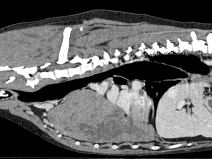

• Journées automnales de l’Est : les vomissements, de la cause aux traitements

L'AFVAC Est organise ses premières journées annuelles portant sur un grand syndrome : le vomissement !

Ce motif de consultation fréquent nous confronte à une grande diversité de causes et de situations cliniques, parfois simples… mais souvent complexes !

Pour en explorer toutes les facettes, des spécialistes en médecine interne, chirurgie, imagerie et nutrition partageront leurs...

ee509eb733e18960964c5a617d1a06c1

Du 24 au 25 septembre 2026

Strasbourg (67000)

Chirurgie

Gastro-Entérologie

Imagerie Médicale

Médecine Interne

Est

2135